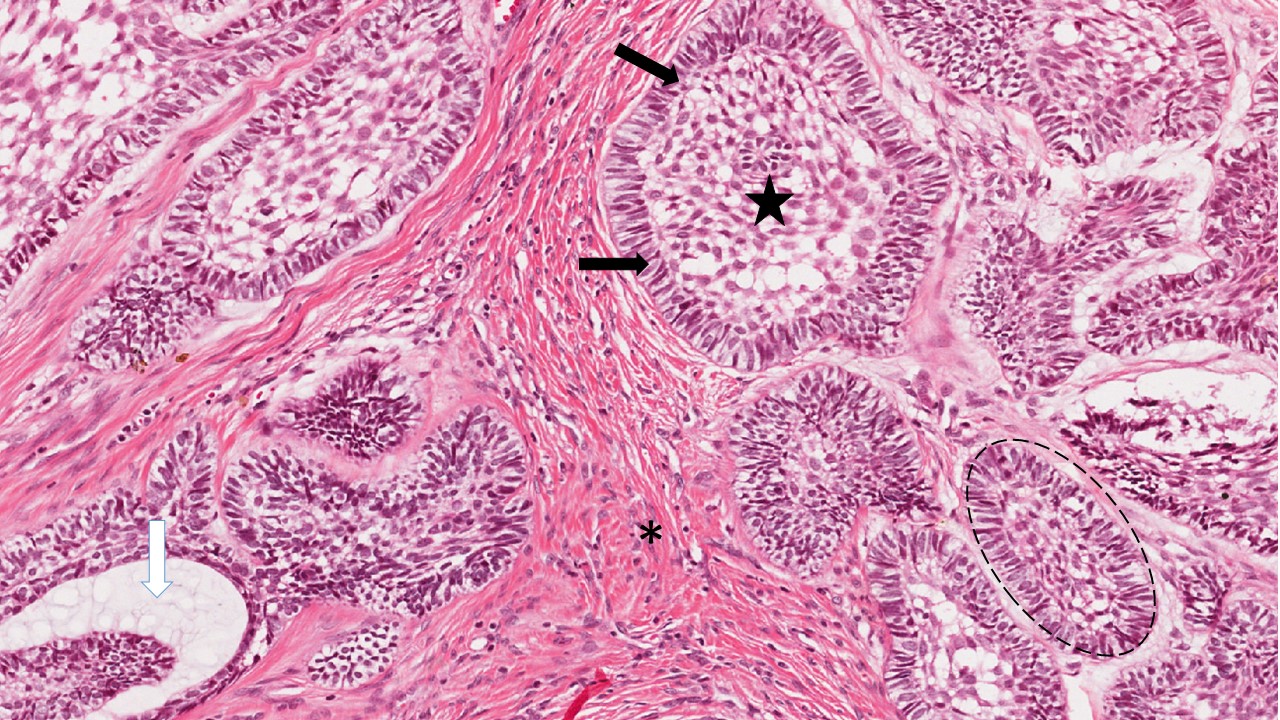

Descrição microscópica:

microscopicamente, o tumor é composto de um tecido mesenquimal rico em células, que lembra a papila dentária primitiva, misturado ao epitélio odontogênico em proliferação. O epitélio odontogênico pode apresentar um padrão de cordões longos e delgados, com frequência anastomosados e/ou um padrão de ilhas de epitélio odontogênico. Em ambos os padrões as células periféricas são colunares altas lembrando pré-ameloblastos e o centro das ilhas apresenta padrão de células epiteliais frouxamente dispostas lembrando o retículo estrelado.

Dados importantes para diagnóstico:

- Cordões de células epiteliais odontogênicas (setas pretas);

- Ilhas de células epiteliais odontogênicas (setas brancas);

- Células periféricas colunares altas empaliçadas (setas amarelas);

- Centro das ilhas lembrando retículo estrelado (asterisco);

- Tecido conjuntivo rico em células com núcleo volumoso e poucas fibras colágenas (estrela).